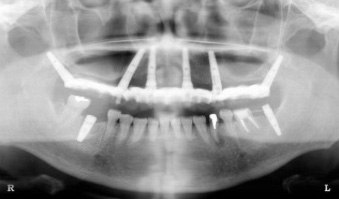

| 翼状突起インプラント | ザイゴマインプラント | |

| 可能な部位 | 一番奥の歯(7番・第二大臼歯) | 一番奥から2、3本目(5番第二小臼歯、6番第一大臼歯) |

| 術後レントゲン(上顎)の一例 | ![]() |

![]() |